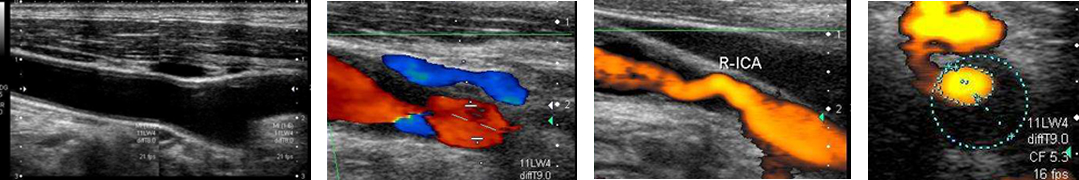

当院では心臓疾患や頚動脈硬化症、甲状腺疾患、腹部疾患については超音波専門検査士による負担のない超音波検査(心臓/ 甲状腺/ 頚部/ 腹部)での詳細な評価を取り入れております。

最新の超音波エコー機種(東芝Xario 200)を導入しております。昨今、未病を発見する上で超音波エコーの重要性は確立しております。検査を希望される方は外来にてご相談下さい